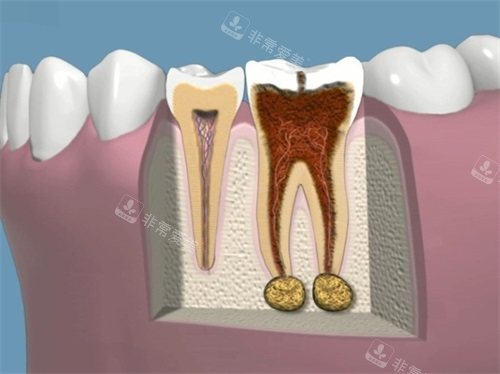

牙齿龋坏根管治疗前